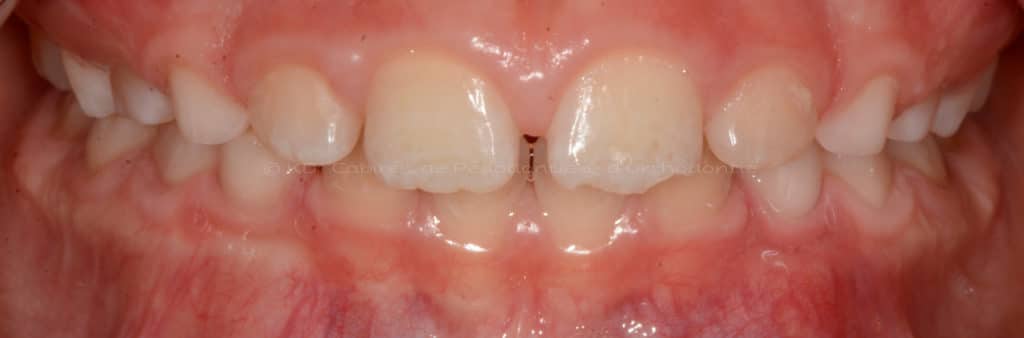

Correction des problèmes d’occlusion en dentition mixte, c.-à-d. à l’âge où l’enfant a des dents de lait et adulte, souvent entre l’âge de 7 ans et 9.5 ans. Le but de ces interventions n’est pas d’aligner les dents, car la dentition est en train de changer.

Cas #2 – Traitement avec un masque de protraction maxillaire en dentition mixte (âge 8.8). Les buts sont de corriger l’articulée croisée, améliorer la position et augmenter la largeur de la mâchoire supérieure.